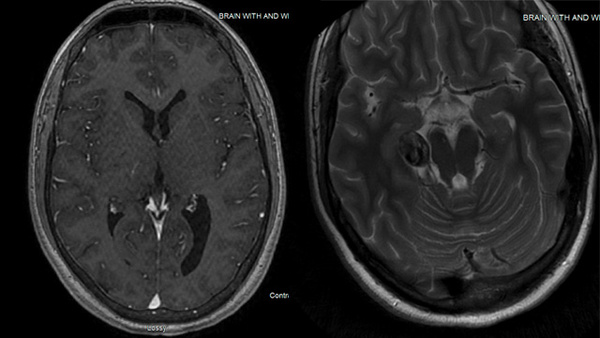

Fusiform Posterior Cerebral Artery Aneurysm Coil Embolization